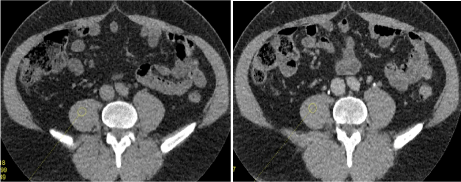

Qualitative evaluation: (Figures 5, 6)

Figure 5. Qualitative evaluation

Figure 5a. Excretory WV mode –sagittal view –result of the automatic stitching (a1). The junctions between volumes are recognized at certain levels (→ white arrow); after additional manual stitching (a2); the junctional zones have disappeared.

Figure 5b. Qualitative evaluation between helical acquisition unenhanced (b1) and excretory WV mode (b2). There is no visual difference for a clinical purpose between those two acquisition modes.